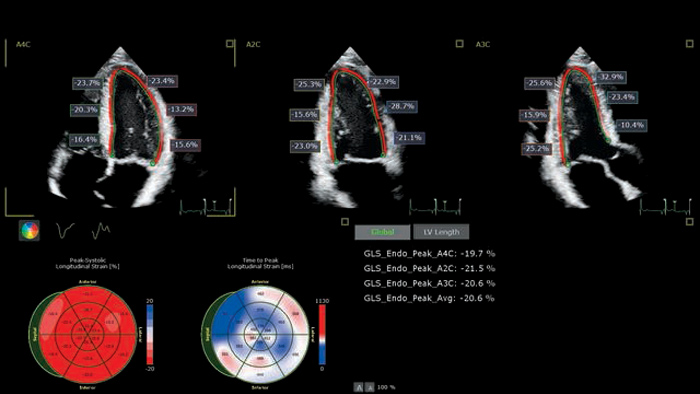

Ultrasound Workspace

Rationalisez les procédures d’échocardiographie au sein de votre organisation avec Philips Ultrasound Workspace. Basé sur la plate-forme TOMTEC ARENA, il permet une meilleure efficacité en matière de visualisation, d’analyse et de création de rapports ; il offre aux équipes de soins la flexibilité nécessaire pour adopter différents processus de travail en fonction de leurs besoins actuels et futurs.

EPIQ CVx

La solution d’échocardiologie dédiée EPIQ CVx offre des fonctionnalités améliorées. Elle vous permet de dispenser des soins de qualité grâce à une puissance de traitement augmentée, une imagerie de qualité avec des détails plus nets & et plus précis et une optimisation de l’efficacité des examens, complétées par les fonctionnalités de quantification éprouvées et fiables d’Ultrasound Workspace.